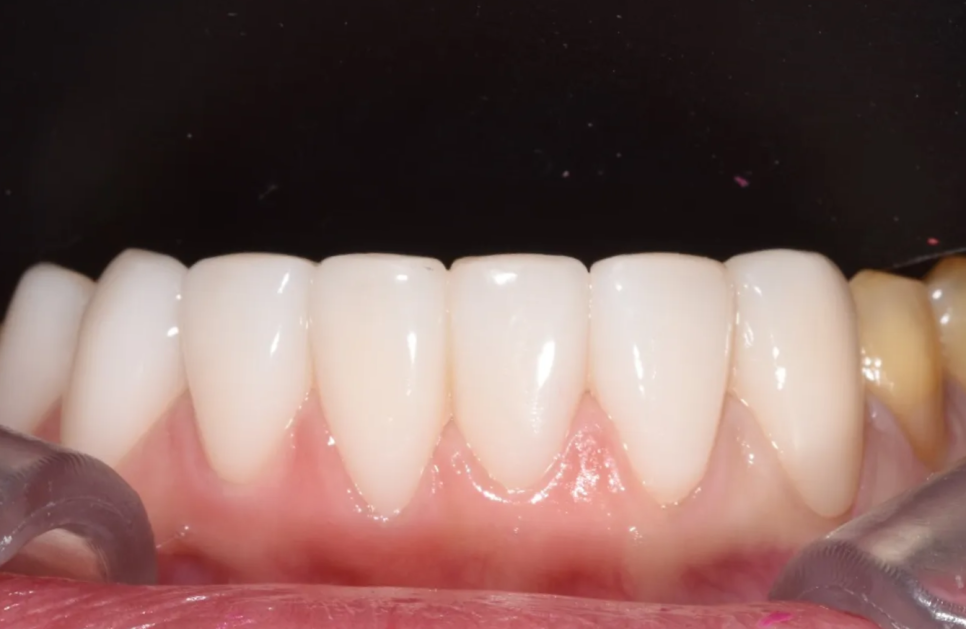

아랫니 결과

치료 후 아랫니

아랫니도 마찬가지로 큰 변화가 있었습니다. 삐뚤어져 있던 앞니가 가지런하게 정렬되었고, 가운데 앞니 사이 벌어져 있던 공간도 자연스럽게 메워졌습니다. 잇몸 경계가 마모되어 있던 부위도 세라믹 레진필링으로 깔끔하게 수복되었습니다.

치료 전과 비교하면 색상, 형태, 잇몸 라인 모두 극적으로 개선된 것을 확인하실 수 있습니다.